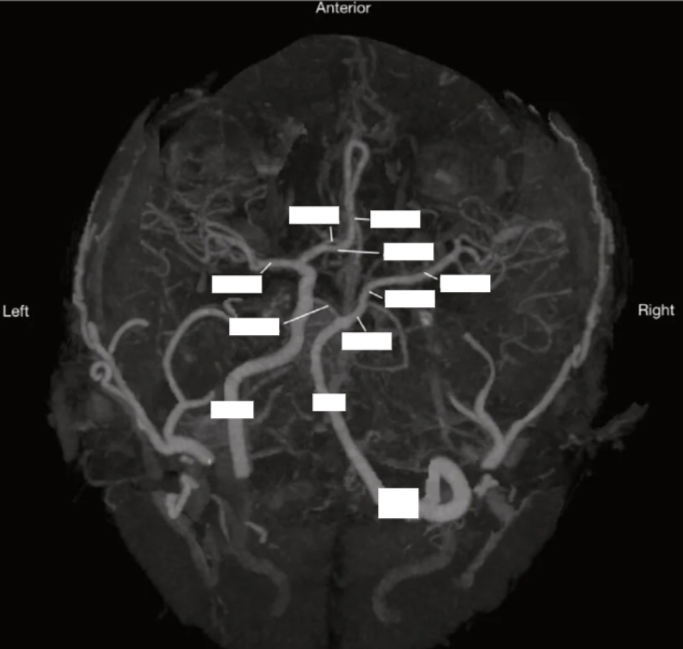

Label the circle of willis

Please label the circle of willis